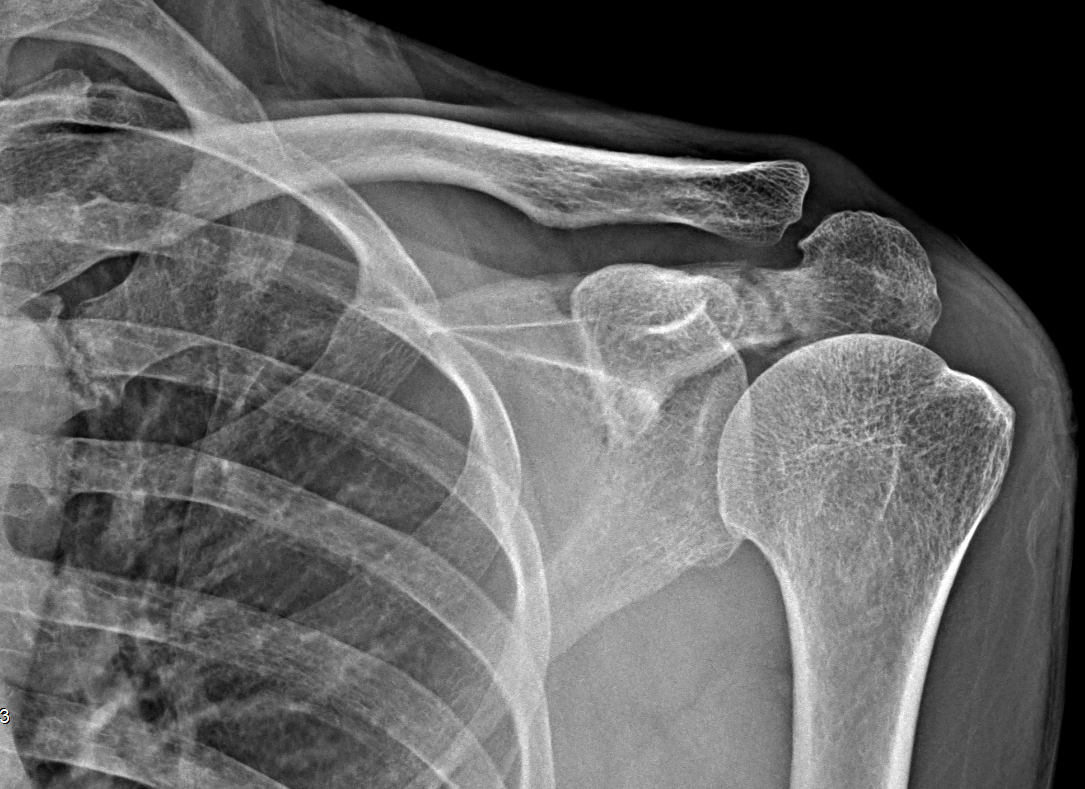

Fracture de l’acromion

Ayush Goel, Radiopaedia.org. From the case rID: 194768

TDM pour éliminer une fracture associée.

Rare, avis chirurgical. Traitement en fonction du déplacement.